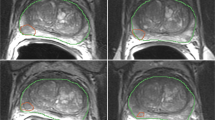

Manual delineation

All 74 individual lesions were manually delineated on T2WI for both scans based on PI-RADS reports by a radiology resident (E.S.) with over 5 years of experience in examining PCa lesions at St. Olavs Hospital, Trondheim University Hospital, Trondheim, Norway using ITK-SNAP [25] (v3.6).